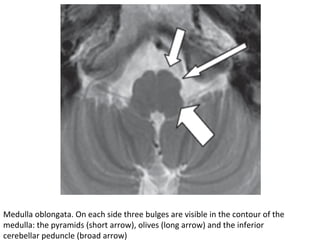

Medulla	oblongata.	On	each	side	three	bulges	are	visible	in	the	contour	of	the

medulla:	the	pyramids	(short	arrow),	olives	(long	arrow)	and	the	inferior

cerebellar	peduncle	(broad	arrow)

The medulla is the most caudal portion of the brain stem and continuous

with the cervical cord at the level of the foramen magnum.

Anteriorly, the pyramid has a protrusive appearance formed largely by

the corticospinal tracts.

Posterior and lateral to the pyramid is a very shallow groove called the

ventrolateral sulcus, in which the vertebral arteries usually lie.

Lateral to the pyramid is the olive corresponding to the inferior olivary

nucleus. Ventrolaterally, the ninth, tenth, and eleventh cranial nerves

emerge from the postolivary sulcus, and the twelfth cranial nerve

emerges from the preolivary sulcus.

Laterally, the inferior cerebellar peduncles, connecting the spinal cord

and medulla with the cerebellum.

-CN12	exits	anterolateral	medulla	in	preolivary	sulcus	while		CN9,

CN10,	&	cranial	roots	of	accessory	CN	11	nerves	exit	lateral	medulla	in

postolivary	sulcus.